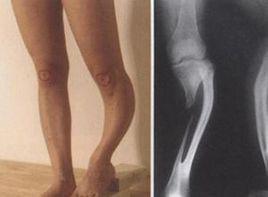

跛行,小腿短縮。可見脛骨弓形畸形,足外翻,外髁消失,並伴發其他肢體短縮畸形。

Ⅰ型:單側部分缺失,小腿可中度短縮,一般無殘疾。

Ⅱ型:腓骨幾乎完全缺失,肢體極短,脛骨在中1/3和下1/3處全弓畸形。皮膚有微凹,但與弓端無粘連;足下垂和外翻;同側股骨也短縮。即使治療,功能也較差。

Ⅲ型:可能為單側,也可能為雙側,並伴有其他嚴重異常,如上肢或股骨畸形,以及脊柱裂等。這種病例較多,預後也差。

依據臨床表現和X線片,診斷即可確立。